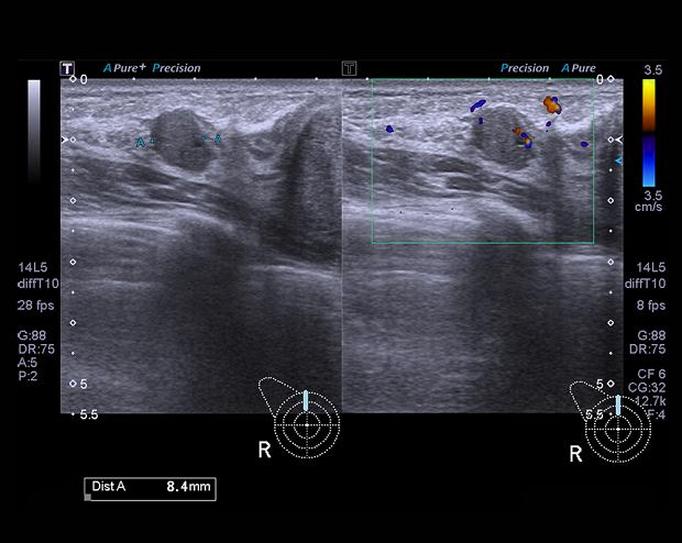

Karmienie piersią staje się okresem niezwykłej bliskości między matką a dzieckiem, a jednocześnie wymaga od nas większej troski o nasze zdrowie. Podczas tego etapu organizm przechodzi liczne zmiany związane z laktacją, dlatego regularne monitorowanie stanu zdrowia, a szczególnie stanu piersi, nabiera istotnego znaczenia. Wykonywanie badań, na przykład USG piersi, umożliwia wykrycie niepokojących zmian już na wczesnym etapie. W związku z tym, mimo że wiele kobiet może mieć wątpliwości co do potrzeby badań w czasie laktacji, warto zwracać na nie szczególną uwagę.

Niewłaściwe przekonania głoszą, że przeprowadzanie jakichkolwiek badań diagnostycznych w czasie karmienia piersią jest niemożliwe. To błędne myślenie! USG piersi okazuje się całkowicie bezpieczne zarówno dla matki, jak i dla dziecka. Co więcej, w wielu przypadkach jego wykonanie jest wręcz zalecane. Ważnym krokiem przed badaniem jest opróżnienie piersi, co pozwala na lepszą interpretację wyników. Obawa przed ewentualnym dyskomfortem nie powinna nas zniechęcać do skorzystania z tej istotnej formy profilaktyki.

Ciekawym aspektem pozostaje fakt, że karmienie piersią, mimo iż zmniejsza ryzyko zachorowania na raka piersi, nie eliminuje go całkowicie. W niektórych przypadkach zmiany nowotworowe mogą dawać objawy przypominające zapalenia piersi, dlatego szybsza diagnostyka ma kluczowe znaczenie i może uratować życie. Z tego powodu każda mama karmiąca powinna dbać o regularne wykonywanie badań USG, przynajmniej raz w roku. Nasze zdrowie nie powinno być odkładane na później, dlatego nie zwlekajmy z wizytą u lekarza, gdy zauważymy coś niepokojącego!

Ciekawostką jest, że badania USG piersi mogą również pomóc w ocenie, jak laktacja wpływa na struktury tkankowe piersi, co dostarcza cennych informacji na temat zmian hormonalnych zachodzących w tym okresie.

W trakcie laktacji w piersiach zachodzą różnorodne zmiany, które mogą utrudniać właściwe diagnozowanie podejrzanych zmian. Skoro już się tu znalazłeś, sprawdź, jak oksytocyna wpływa na ból podczas porodu. Mimo to doświadczony lekarz potrafi skutecznie zinterpretować wyniki USG, nawet w takiej sytuacji. Co więcej, warto zgłosić się na badanie także wtedy, gdy wydaje Ci się, że wszystko jest w porządku. Często, ponieważ okres laktacji trwa dłużej, możesz odczuwać opóźnienia w decyzji o wizytach. Jak wiadomo, lepiej jest trzymać rękę na pulsie, niż czekać na coś niepokojącego i nieprzyjemnego.

Ciekawostka: W trakcie laktacji piersi kobiety mogą być bardziej wrażliwe, co czasami prowadzi do błędnych wniosków o obecności guzów; dlatego regularne USG jest kluczowe, aby rozwiać wszelkie wątpliwości i zadbać o zdrowie mamy i dziecka.